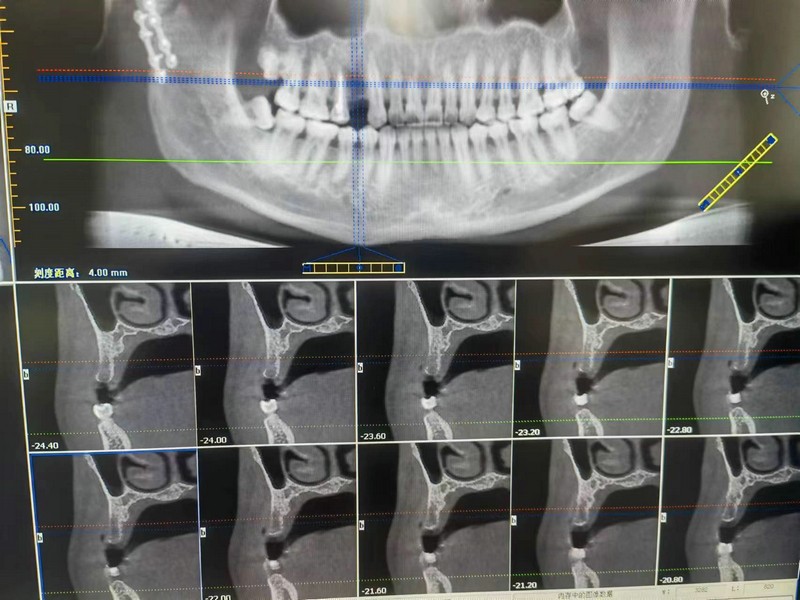

患者陳某某,武山縣人,該患者自去年3月份外傷后導(dǎo)致上頜多發(fā)性骨折,牙列缺損,口腔咬合咀嚼功能受損,影響正常生活質(zhì)量,到市二院口腔科擬種植修復(fù)。CBCT示術(shù)區(qū)重度水平型骨缺損合并垂直型骨缺損,常規(guī)種植和GBR骨增量無法提供植體初期穩(wěn)定性。術(shù)前,經(jīng)與患者及家屬溝通,確定“自體骨移植口腔種植手術(shù)”方案。頜面外科主任高小平和口腔副主任醫(yī)師安小斌在門診手術(shù)室護理人員的密切配合下,在患者同側(cè)下頜骨外斜線處取0.6×11mm矩形骨塊,嵌入術(shù)區(qū)骨缺損處,覆蓋人工骨膜,嚴(yán)密縫合創(chuàng)面,口外四頭帶加壓包扎。CBCT顯示植體植入符合手術(shù)預(yù)期指標(biāo),術(shù)后解決了該患者的牙列缺損修復(fù)難題。